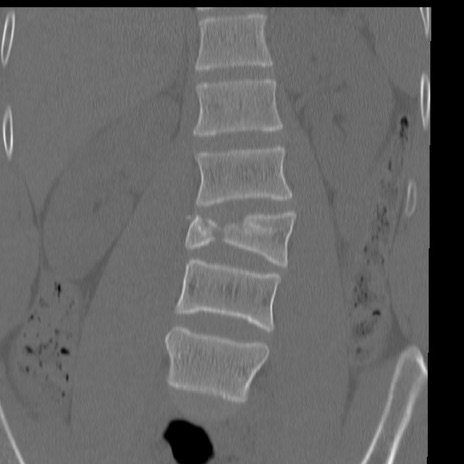

症例3 腰椎CT(冠状断像)

腰椎CT